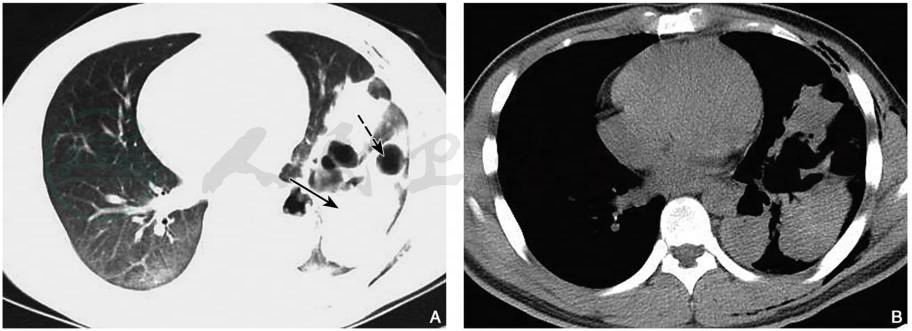

图6肺挫裂伤(“磨玻璃气-液平囊腔征”)

男性,24岁,胸部CT平扫肺窗显示右肺下叶片状磨玻璃样高密度影,内见多发结节状高密度影,部分内见“气-液平面”(箭)